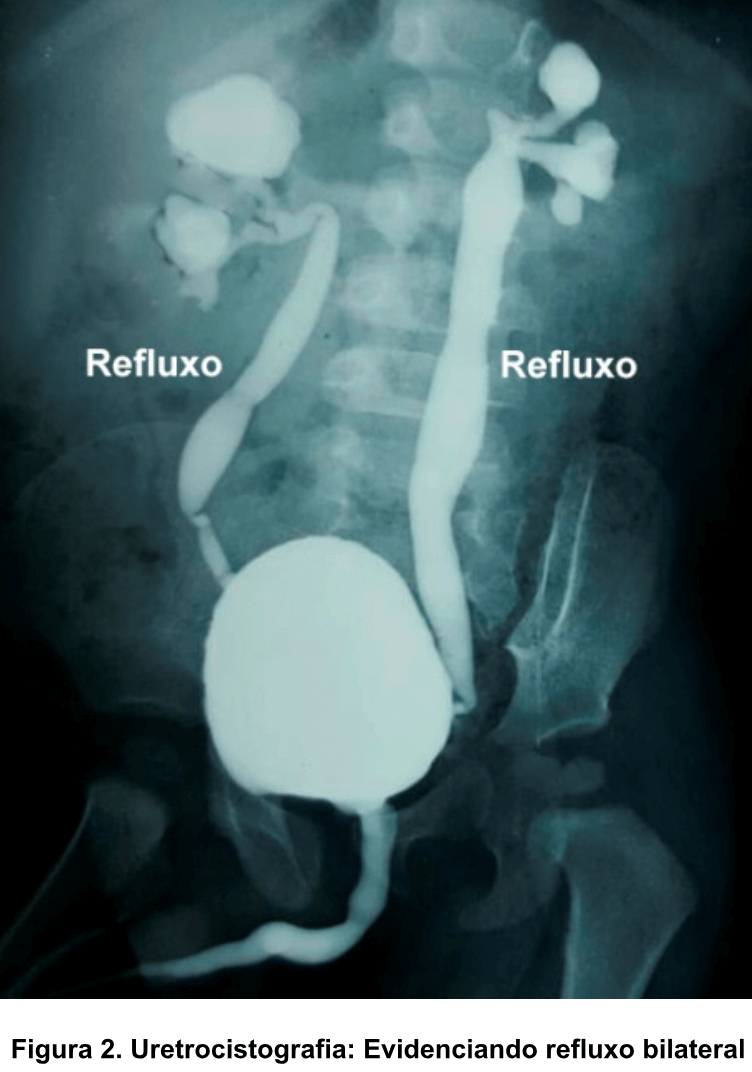

Refluxo vesicoureteral

Retorno da urina da bexiga para o ureter

Uretrocistografia miccional

Diagnostica refluxo (RVU) e qual o grau

Exames que diagnostica os graus de refluxo vesicoureteral? Quais graus possuem mais chance de recorrência de ITU e o que fazer?

Graus III, IV e IV: menos chance de regressão espontânea, mais chance de recorrência de ITU

…QUIMIOPROFILAXIA até resolução de RVU ou até cirurgia

*cefalexina <2anos, nitrofurantoina, bactrim